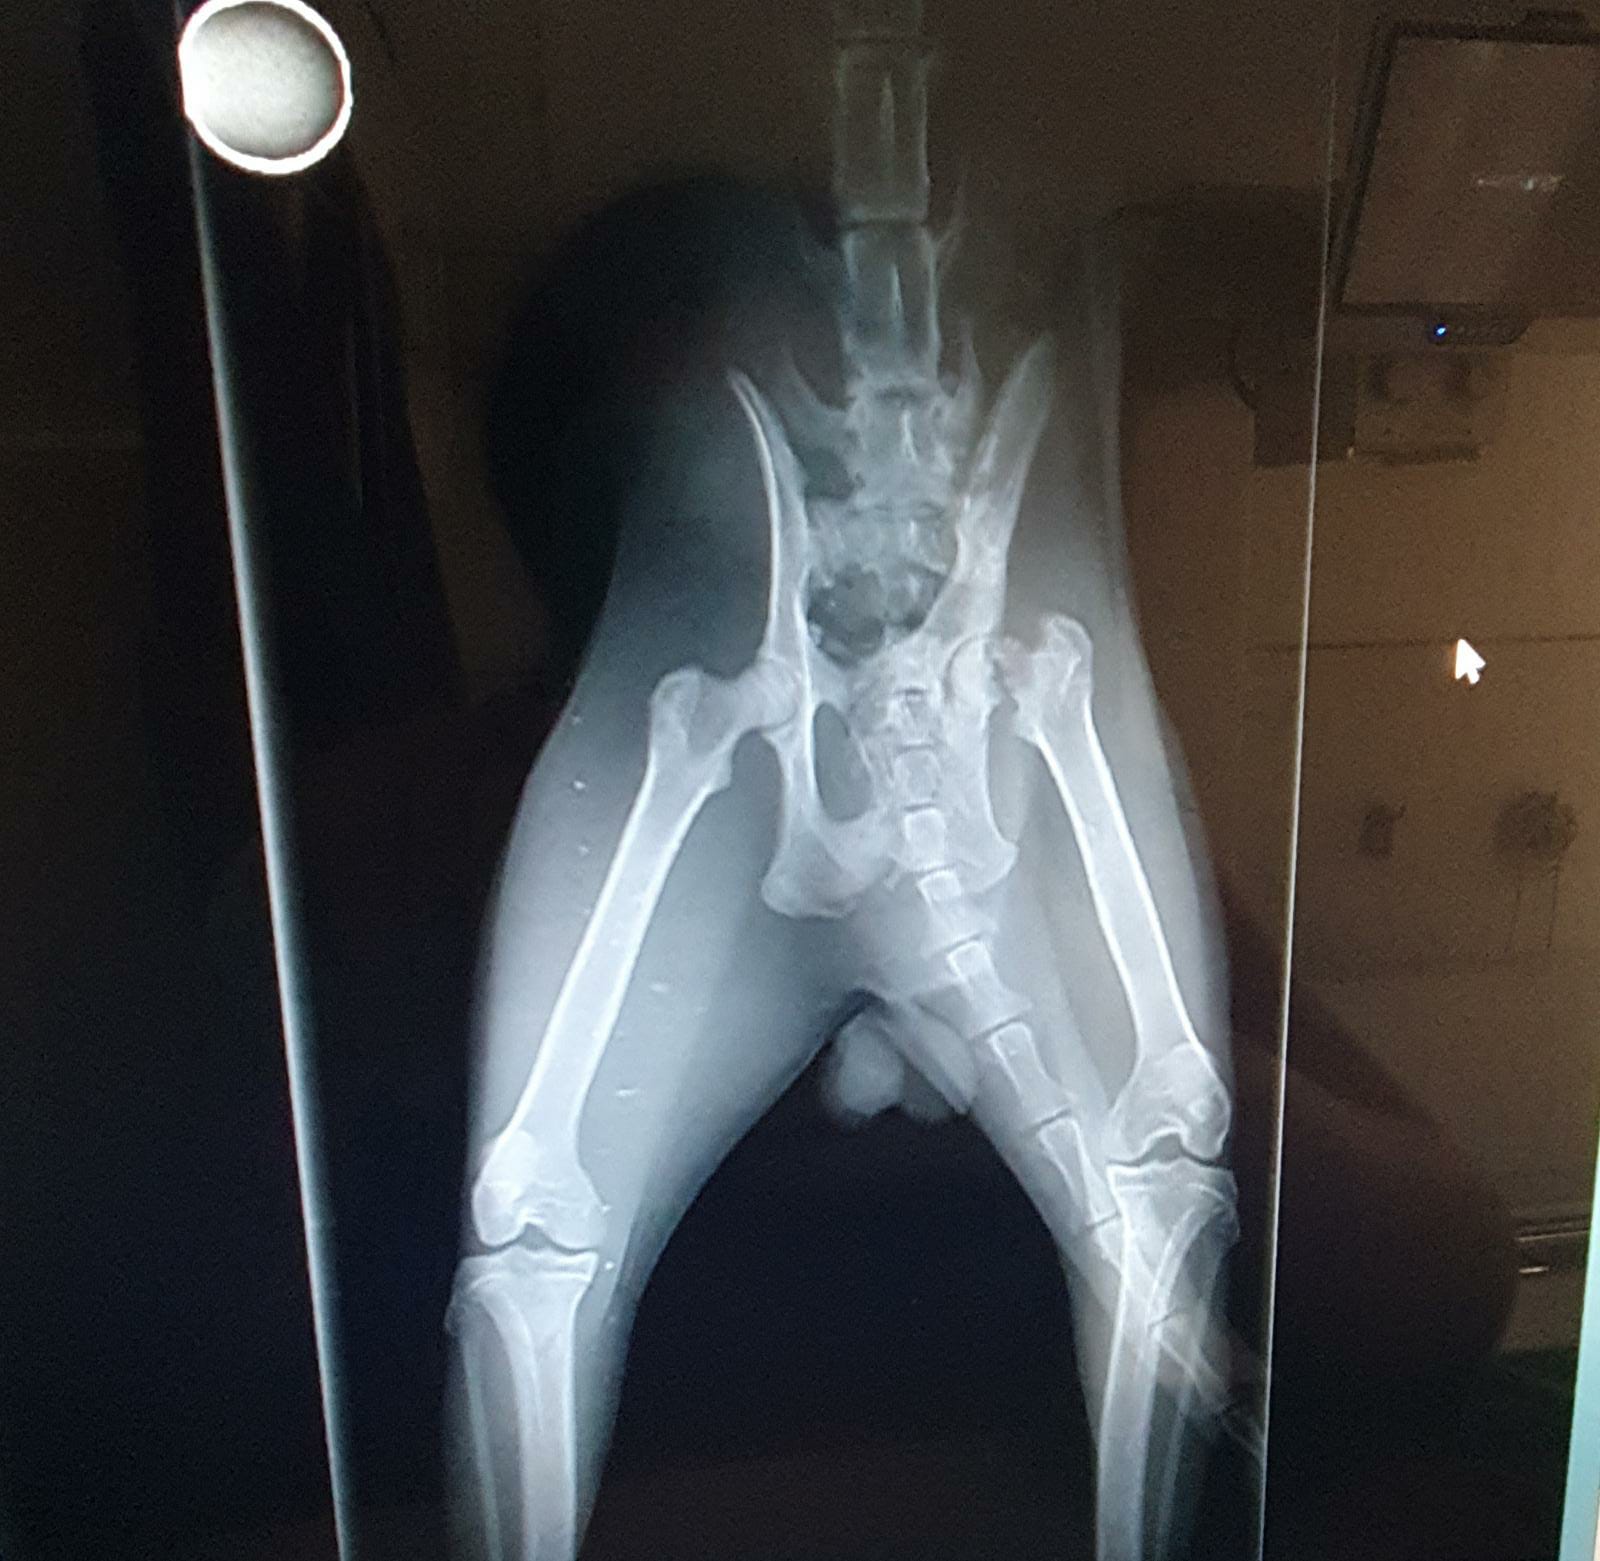

Ahora tienes un problema más: hambre, pulgas y un fémur y cadera rota. Lloras de dolor, pides ayudas a todos lo que pasan a tu lado, casi pierdes la esperanza, cuando por fin alguien se fija en ti.

Para hacerlo las voluntarias que te cuidan necesitan recaudar 500 euros para la operación de tu cadera y fémur. Lo mejor de la vida es gratis dicen, y es cierto; pero para disfrutarlo hay que estar bien y yo no lo estoy.